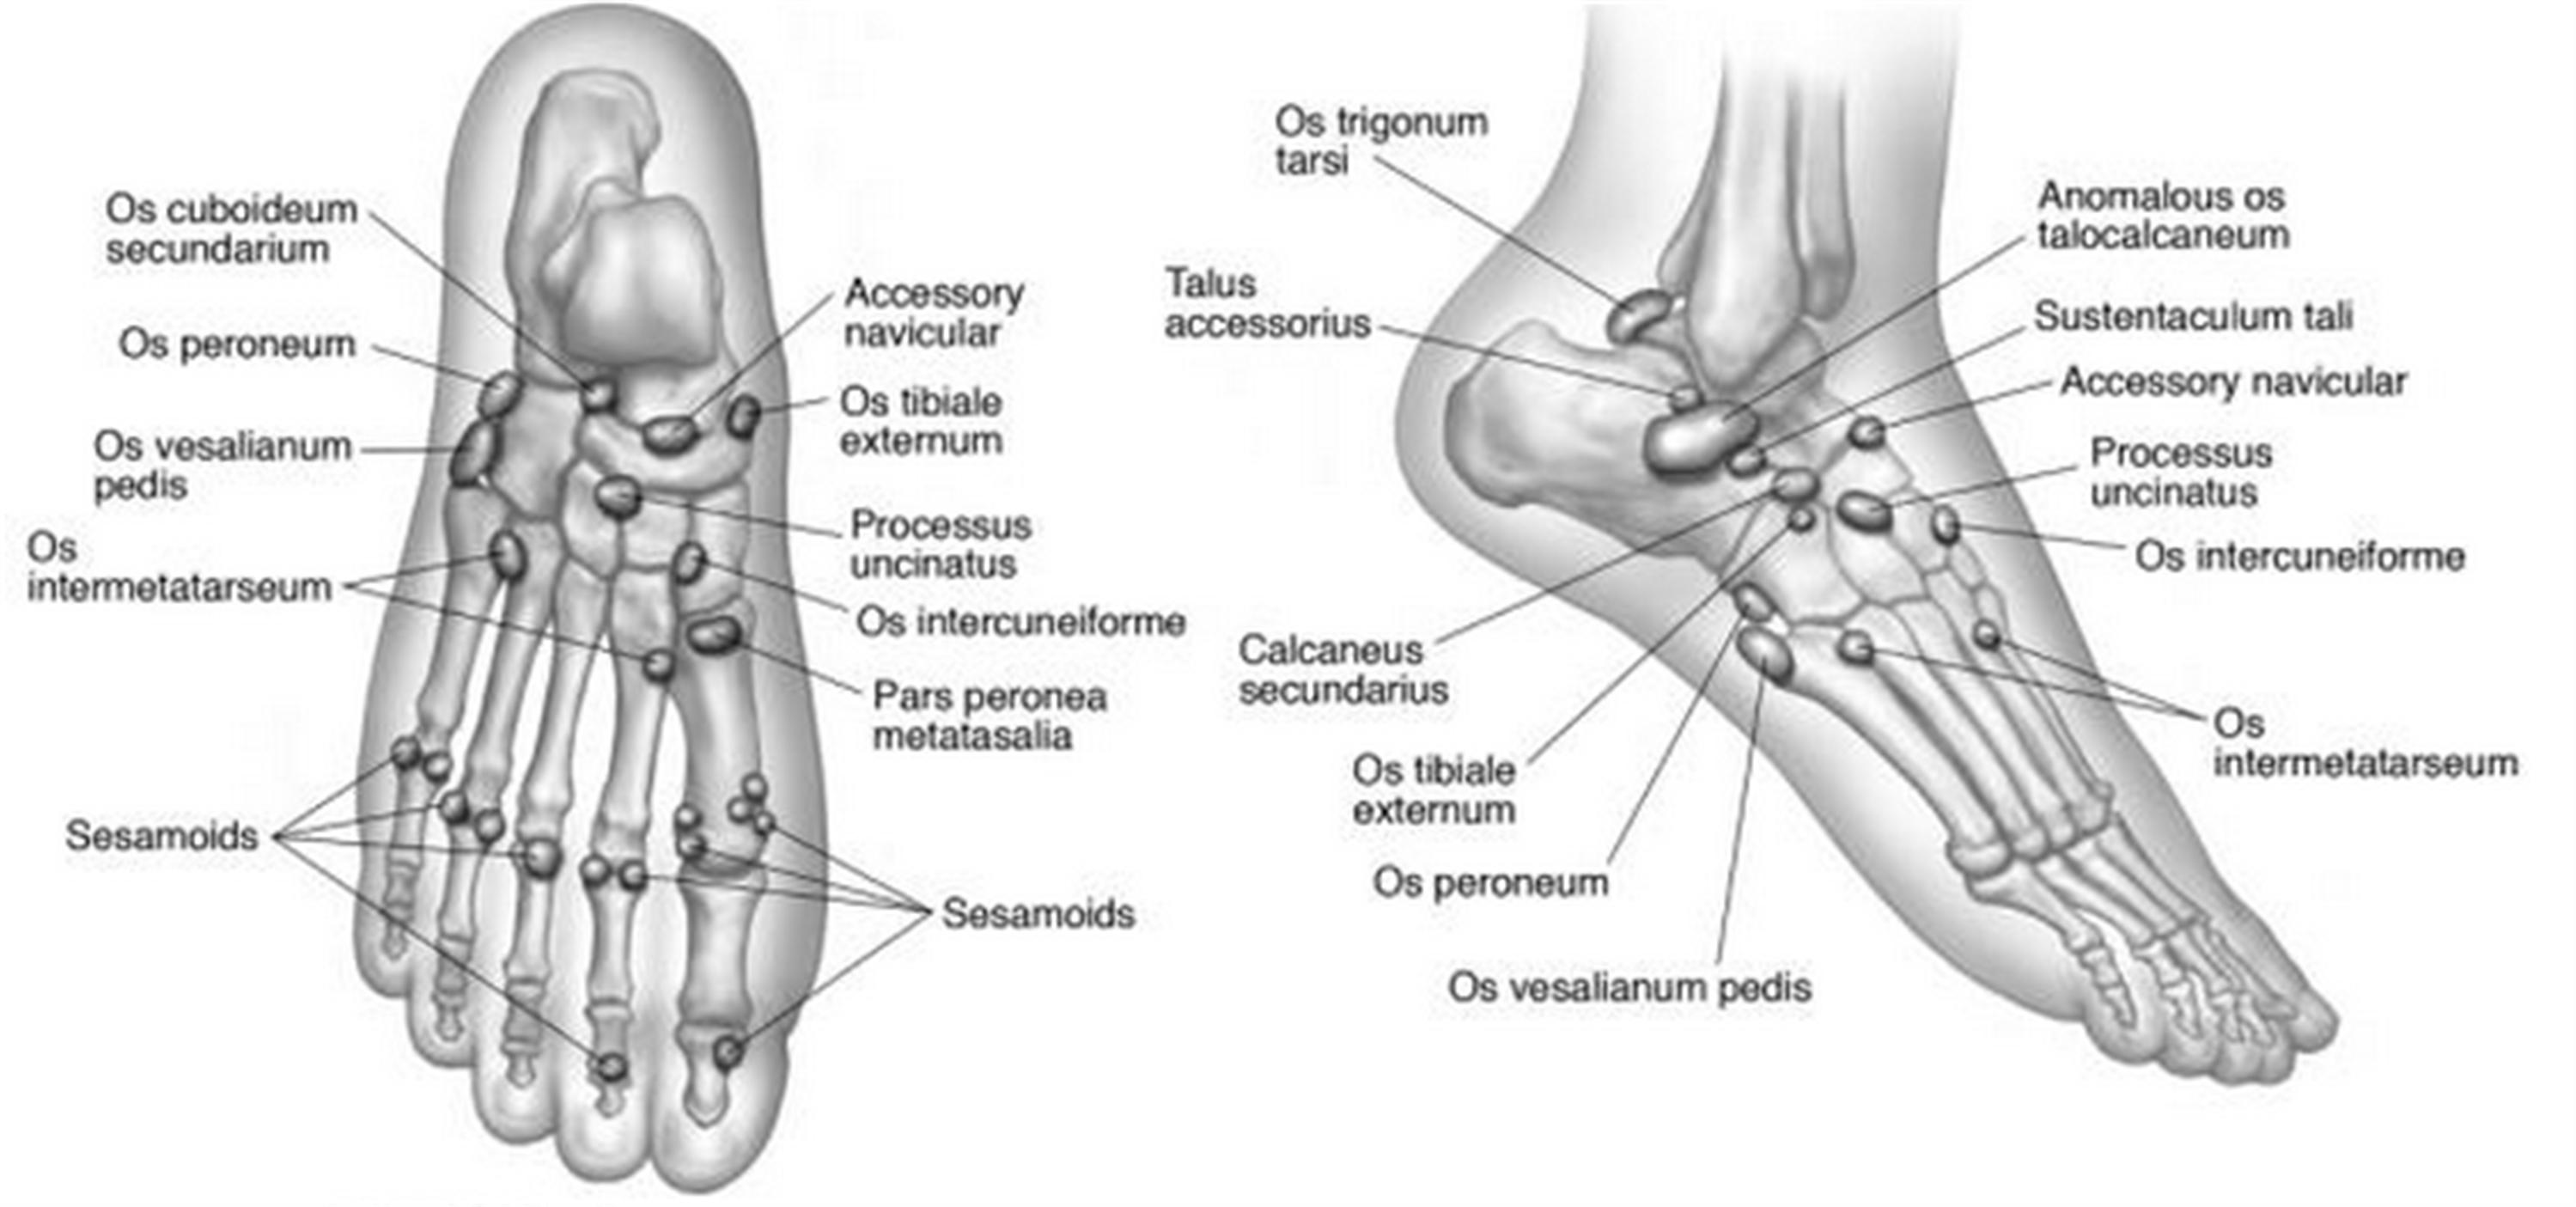

족부에만 40개 넘는 부골이 생길 수 있습니다. 부골이란 것은 대부분 2차 골화중심이 유합되지 못한 채 유지되는 상태로 성장이 끝나게 되면 다음과 같은 작은 형태의 뼈 모양으로 남게 됩니다.

운동선수의 경우 부상이 흔하기 때문에 새끼발가락 끝쪽 부분의 중족골 골절로 의심하고 오는 환자분들중에

Os vesalianum 이나 Iselin disease(traction apophysitis) 등을 함께 감별을 해주어야 합니다.

Sesamoid 라는 종자골이 있거나, 없는 사람들도 있습니다.

Tibialis posterior가 붙는 내측에 위치하는 배모양의 주상골에서도 부골이 있어 통증이 있는 경우도 있습니다.

발 뒤꿈치 쪽, talus 후방 부위에 생기는 Os trigonum 도 incidence 가 꽤 높습니다.